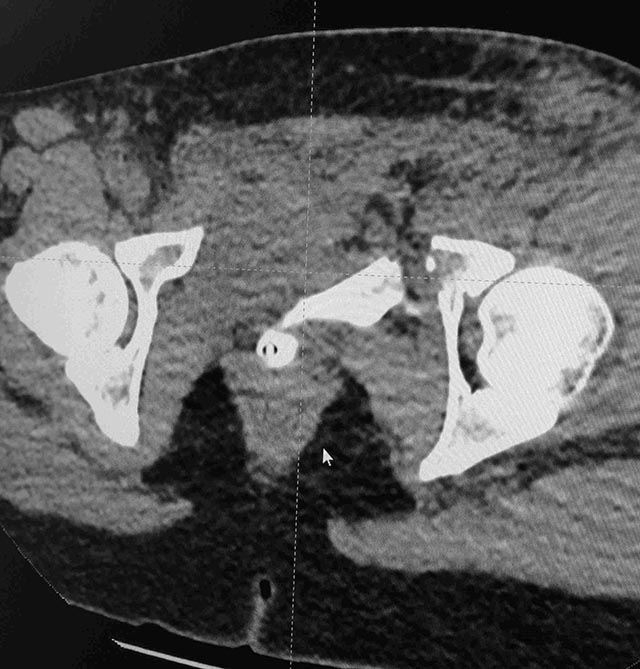

Женщина,21, социальна, без вредных превычек, сбита авто.

Кожа не повреждена. Других повреждений нет. Гемодинамически стабильна. травме 2 сут. Планируем спереди открыто через Stoppa, далее сзади крестец и ость закрыто (крестец может через обе массы?). Интересует мнение по альтернативным вариантам и по предложенному (tricks and shots). Заранее благодарен.

PS Только часть скринов с body scan, один с контрастированием пузыря.